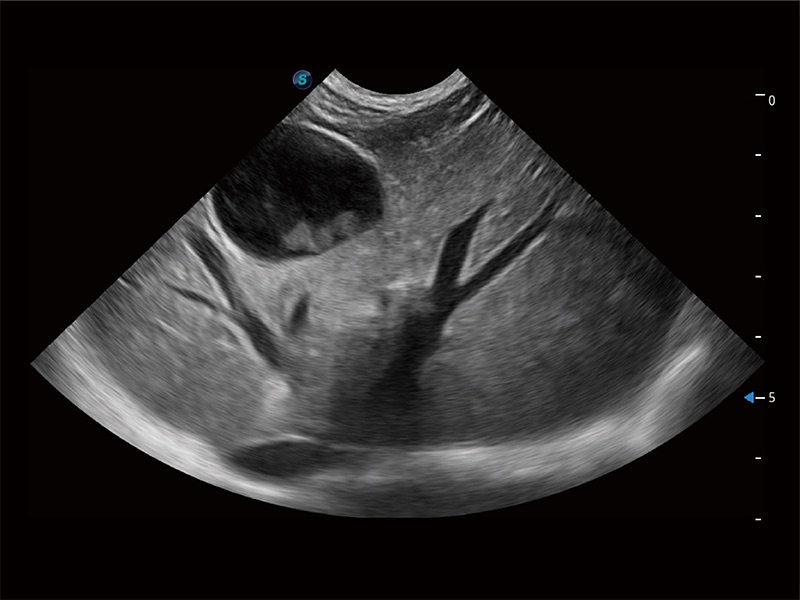

ProPet 80 配備了豐富的心臟探頭群、先進(jìn)的成像技術(shù)和專業(yè)的心臟測量工具,可幫助動物醫(yī)生為不同體型和生理結(jié)構(gòu)的動物提供心臟和心肌功能的全面評估。

ProPet 80 專為動物醫(yī)生設(shè)計,對不同的動物體型和生理結(jié)構(gòu)作出了針對性的優(yōu)化。通過動物影像專用軟件,可滿足個性化的應(yīng)用需求,幫助動物醫(yī)生獲得更精確的診斷數(shù)據(jù)。

ProPet 80 全新的動物超聲智能軟件和豐富的探頭群,為動物醫(yī)生提供了高清晰度和精細(xì)分辨率的圖像,無論在寵物、馬科、畜牧還是實(shí)驗(yàn)室動物等應(yīng)用中都可以輕松應(yīng)對,為您的日常工作帶來滿意的體驗(yàn)。